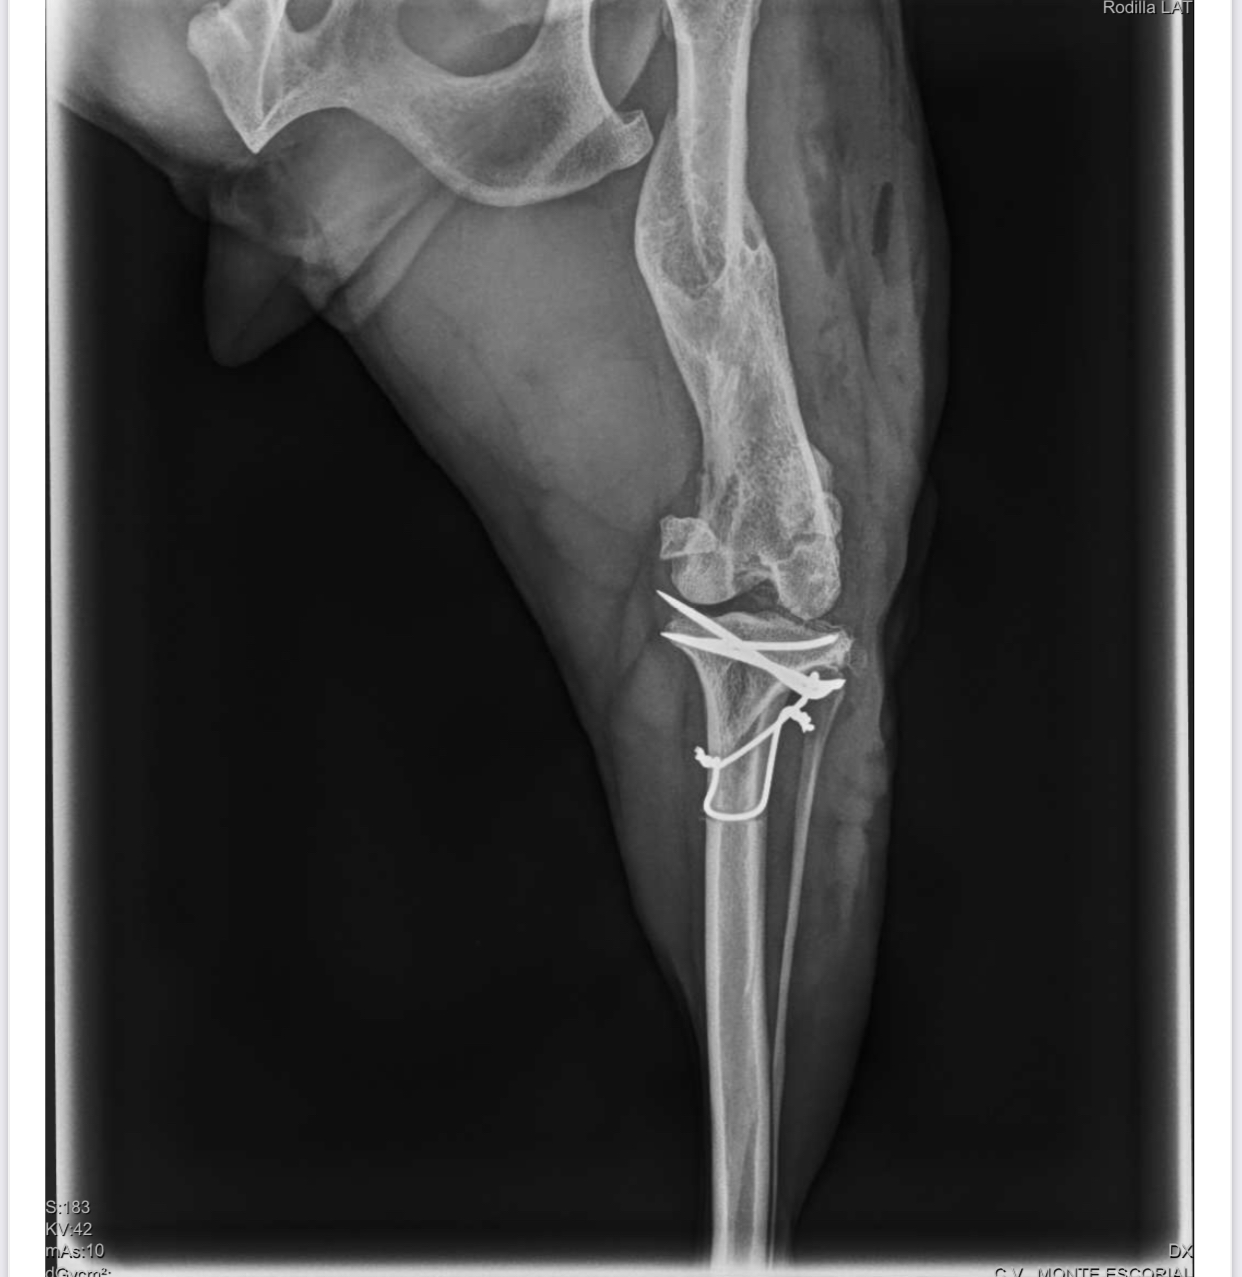

- SKADI: La podenca que llegó con fractura de pata; la han operado y ahora está en proceso de recuperación.